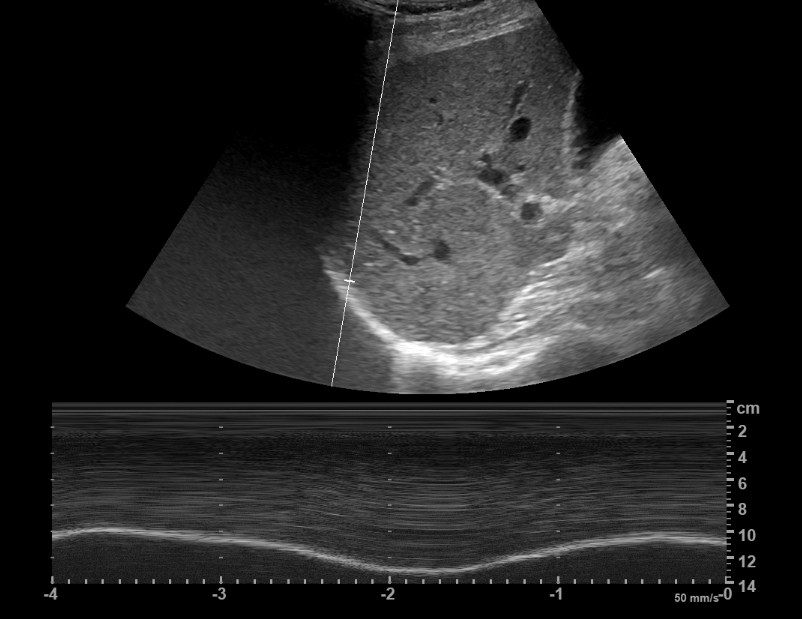

La Frecuencia y la Imagen Dinámica (Modo M)

El modo M, utilizado para evaluar movimientos en tiempo real, como los cardíacos o vasculares, se beneficia de una adecuada selección de frecuencia. Esto optimiza la claridad de los movimientos observados, facilitando diagnósticos precisos en estructuras móviles.

Video

La grabación de video en ecografía permite documentar secuencias en tiempo real, como el movimiento del corazón o el flujo sanguíneo en un vaso. Esto es especialmente útil en estudios dinámicos, como los realizados con Doppler color, donde las imágenes fijas no capturan adecuadamente la funcionalidad o el patrón de flujo observado.